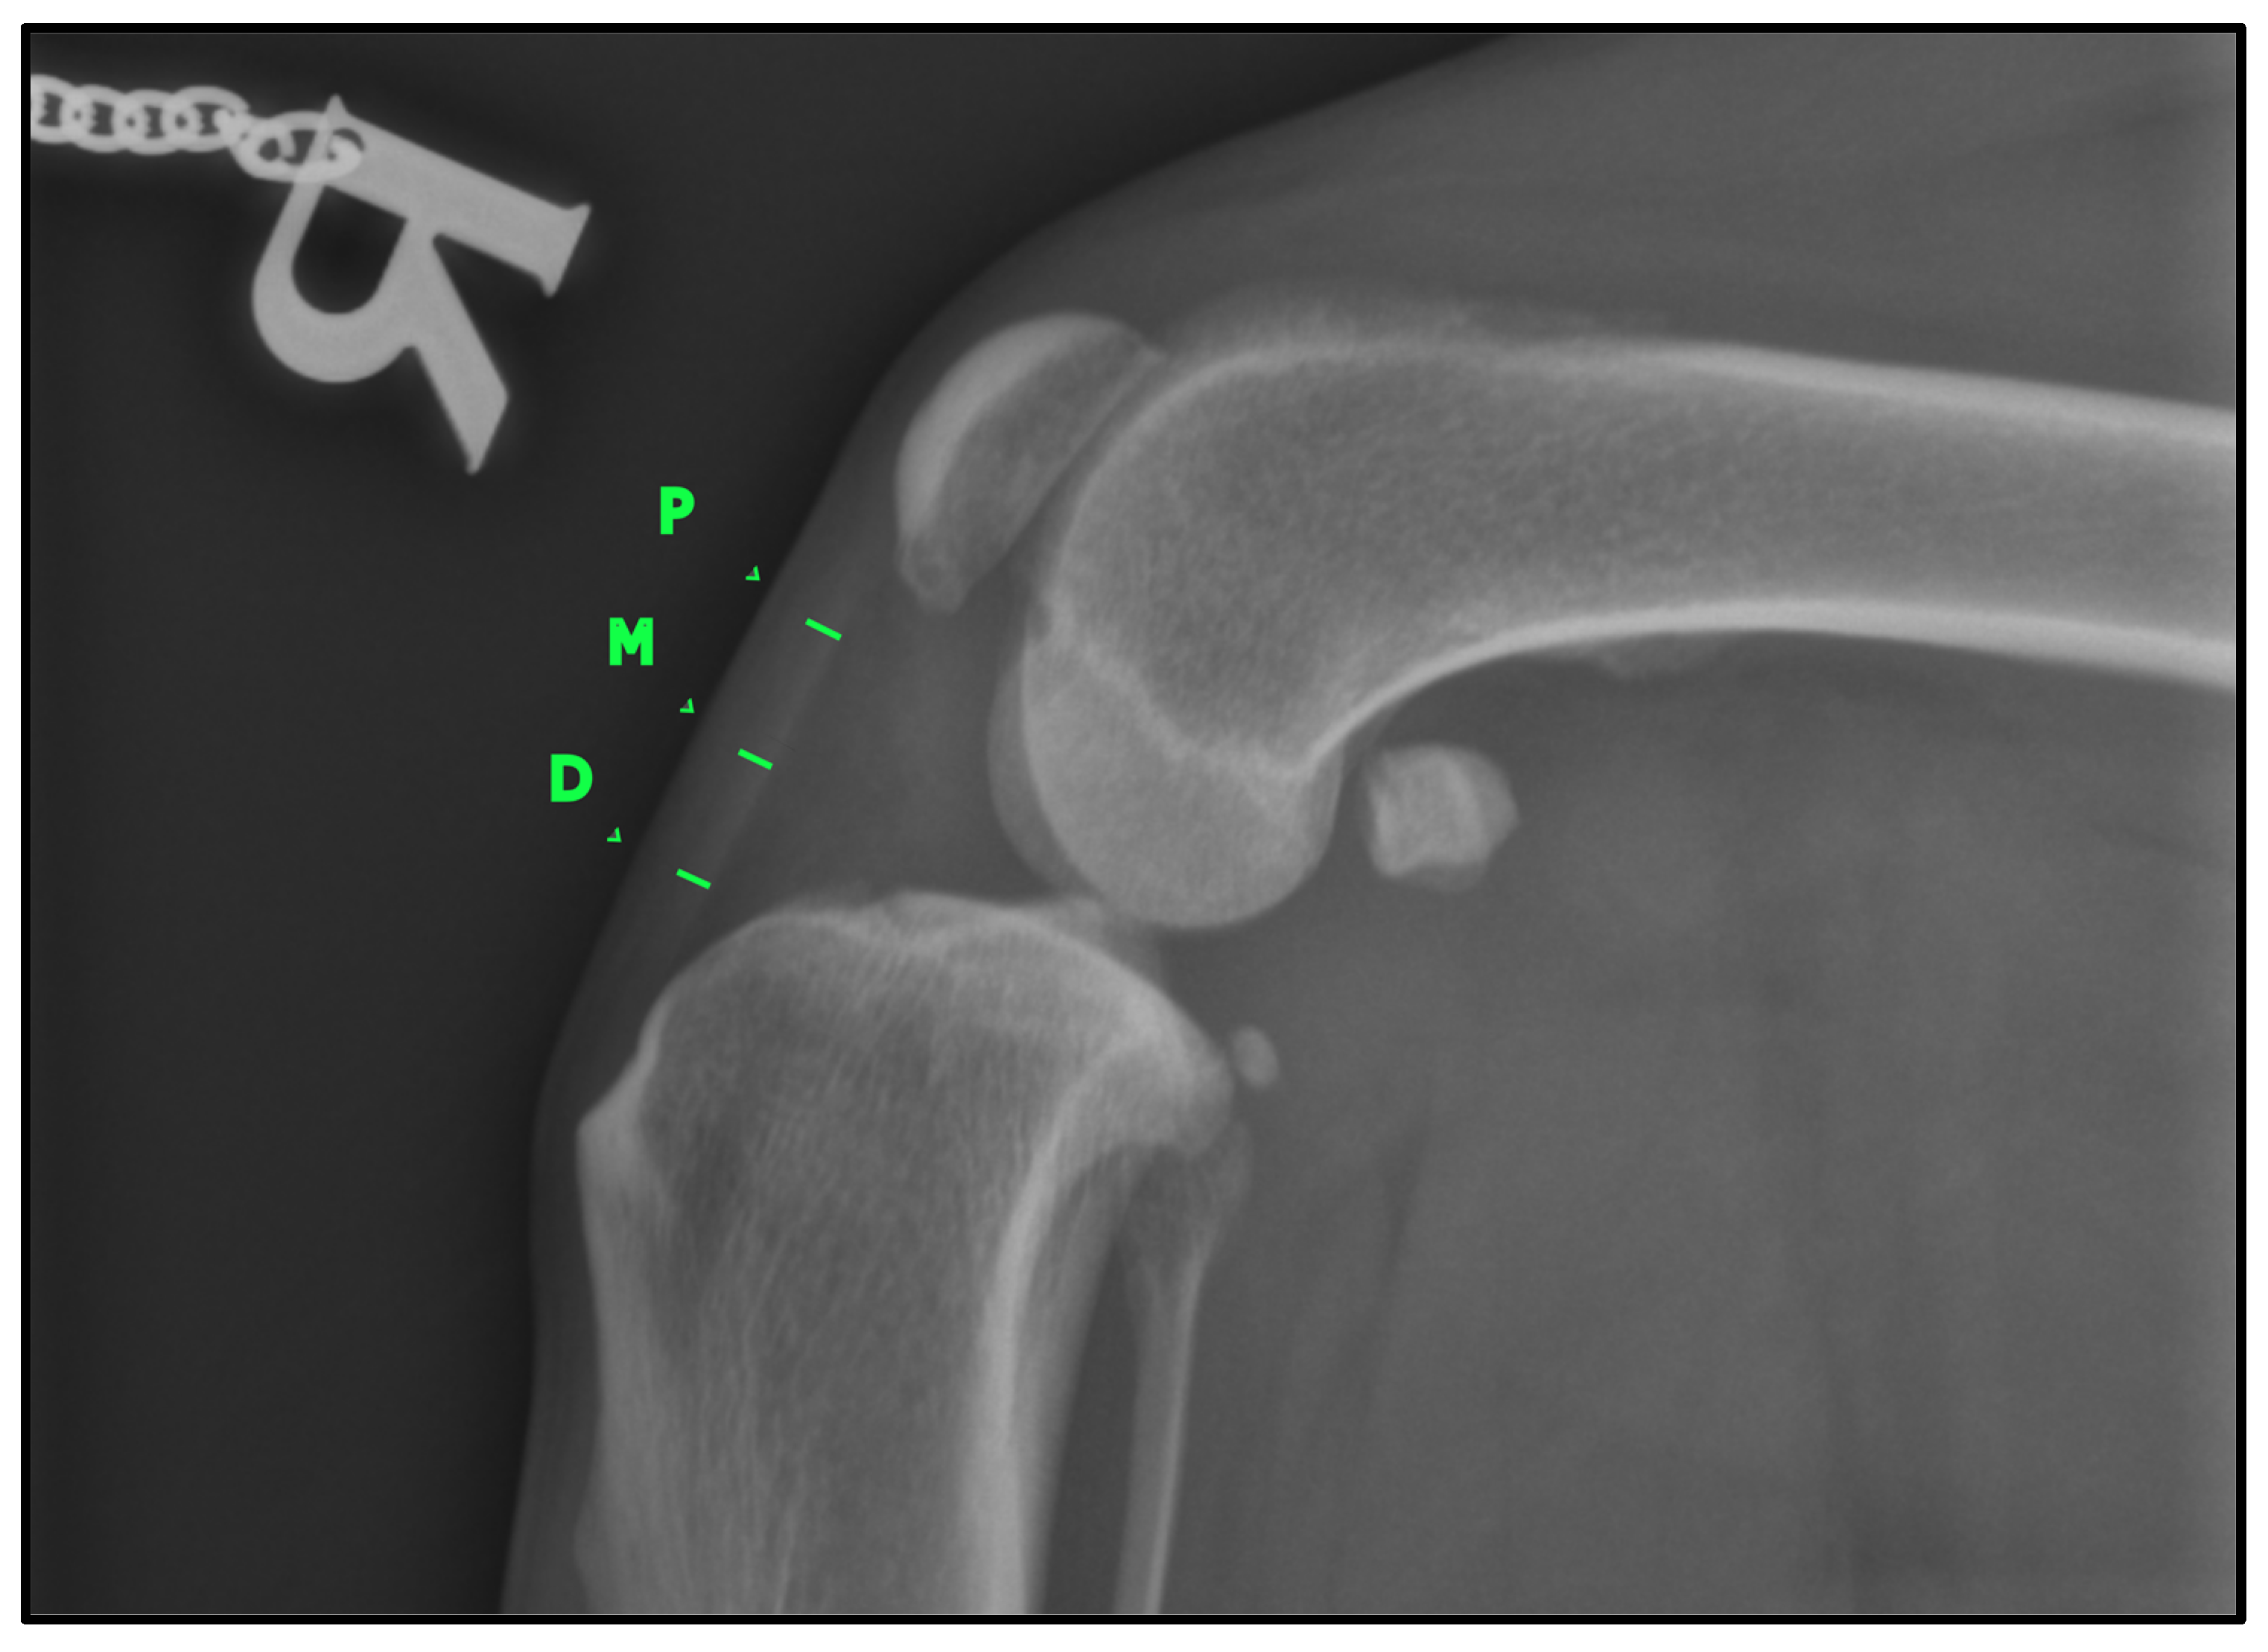

To determine the thickness of the patellar ligament (Figure 2), we followed the method previously described by DeSandre-Robison et al. (2017) [14]. To standardize measurements across patients, the total length of the patellar ligament was first measured from its proximal insertion at the patella to its distal insertion at the tibial tuberosity. This total length was then divided into four equal segments. The ligament thickness was measured at the three junction points between these segments, ensuring that reference points were proportional to ligament length in each patient. Taking this into account, three points were measured in every patient: one proximal, one distal, and one in the middle of the ligament.

Figure 2.

Lateral knee radiographic view (LL) illustrating the measurement of patellar ligament thickness. The ligament was divided into four equal segments, and thickness was recorded at three predefined reference points: proximal (P), middle (M), and distal (D). These measurement locations are marked in green for clarity.